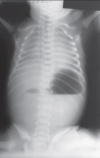

What are 5 features of a congenital diaphragmatuc hernia?

5 B’s:

- B: Bochdalek (name)

- B: barrel chest appearance

- B: back / lateral (usually on the left)

- B: baby (rarely present in adulthood)

- B: bad (associated with pulmonary hypoplasia and high mortality risk)

How common is congenital diaphragmatic hernia?

What is the pathophysiology of CDH?

Why is mortality of CDH so high?

Mortality is 50%

Herniated viscera may have cause lung hypoplasia causing high mortality after birth

What is the management of CDH?

Large nasogastric tube is placed and suction applied to prevent distension of the intrathoracic bowel

Surgical repair after stabilisation

What is the most common type of CDH?

Left sided herniation of bowel through the posterolateral foramen causing heart sounds to be displaced to the right side

AKA Bochdalek hernia (accounts for 85% of cases)